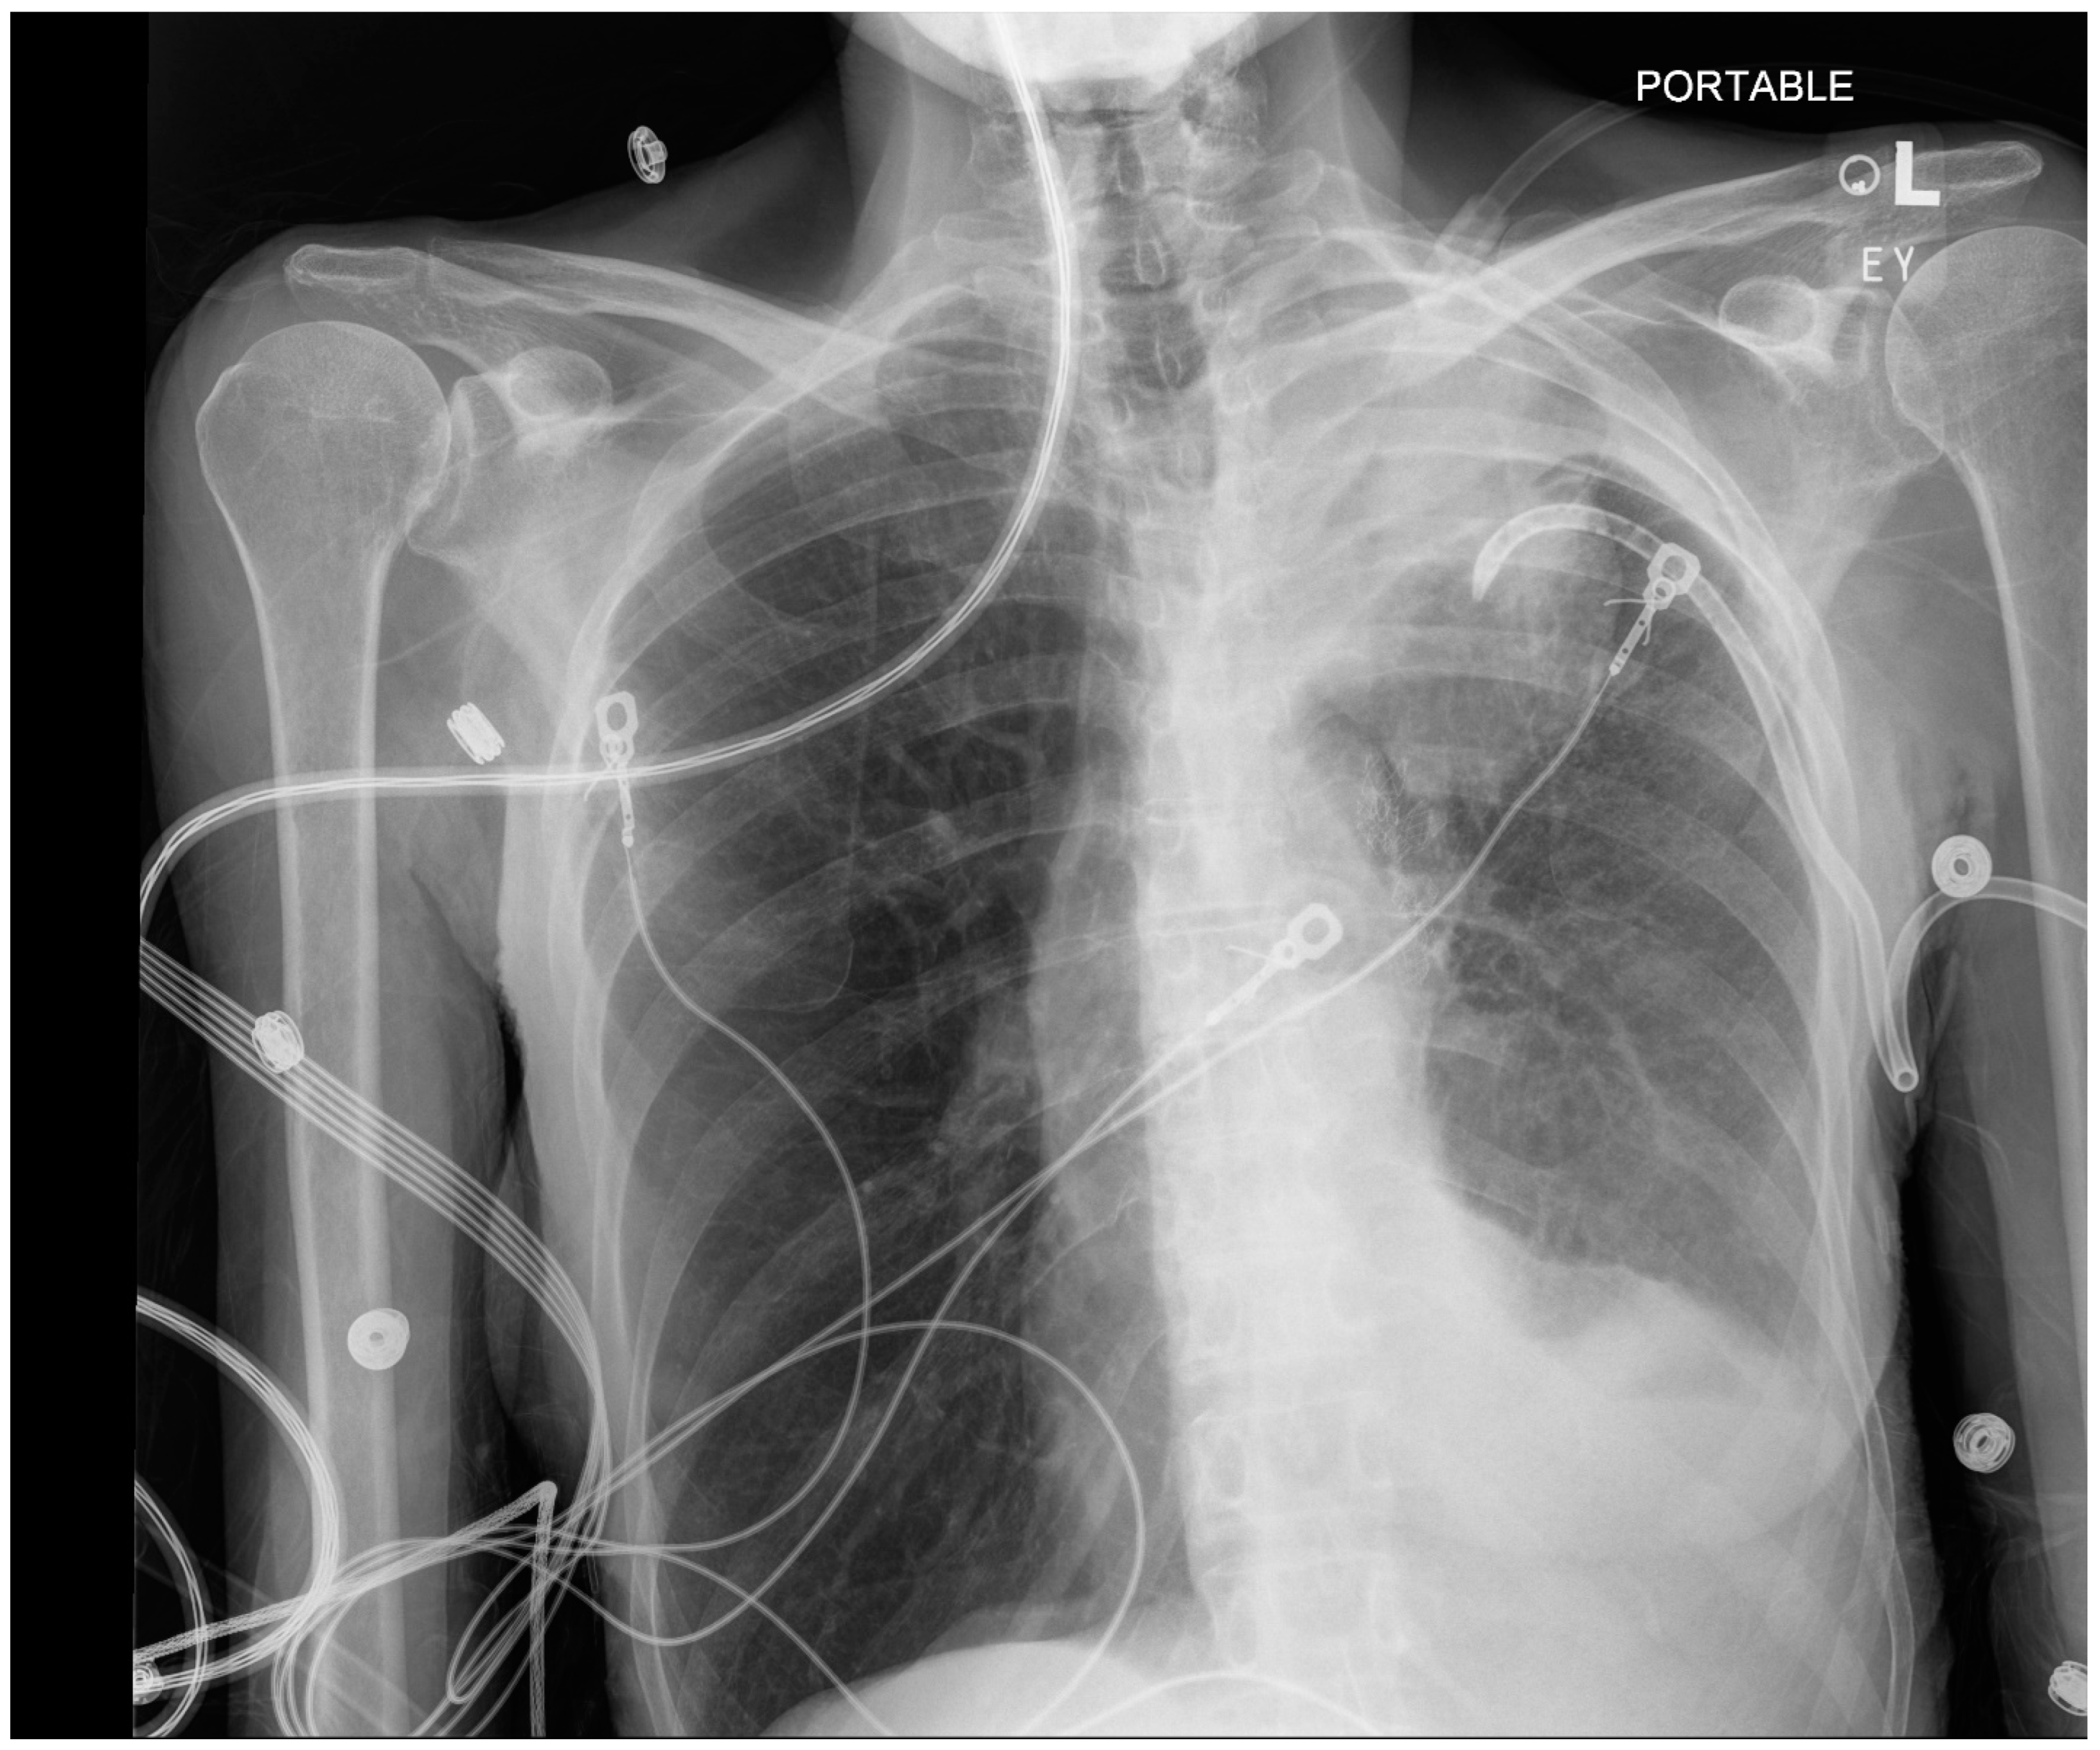

| Procedure | Indication and Preprocedural Factors | Anesthesia Requirements | Post-Procedure Factors |

|---|---|---|---|

| Navigational Bronchoscopy | Biopsying suspicious lesions. Patients are typically elderly with a history of smoking. | General anesthesia, usually TIVA with muscle relaxant. Larger than normal ETT (8.5) Avoid atelectasis without comprising safe oxygenation (SpO2 about 94%). Avoid 100% O2 even for induction. Air O2 mixture for maintenance. ETT position as guided by the bronchoscopist. Use appropriate ventilatory strategy to prevent atelectasis such as VESPA or LNVP (see text for details). Avoid barotrauma and hemodynamic instability during recruitment maneuvers. | Pneumothorax (3.4% to 9.8%). Respiratory failure and difficulty in extubation (rare). |

| Endobronchial valve placement | For lung volume reduction in selected cases of severe COPD | General anesthesia, TIVA with muscle relaxant. Larger than normal ETT (8.5) Hypotension to be expected and often requires phenylephrine support. | Pneumothorax is common, including tension pneumothorax. Incidence is reported as 4.2–34.4% (more often under GA than sedation). COPD exacerbation. |

| Bronchial thermoplasty | Indicated in selected patients with stable asthma without active respiratory tract infection. Should not have exacerbation of asthma for 2 weeks. Before BT, COPD to be excluded. Expect patients to have received steroids before procedure. | General anesthesia, glycopyrrolate for its antisialogogue properties, TIVA with muscle relaxant, ETT or an LMA. | Bronchospasm during or after bronchoscopy. Laryngospasm, atelectasis due to fibrin plugs. Exacerbation of asthma. Lower respiratory tract infections. Bronchial artery pseudoaneurysms. |